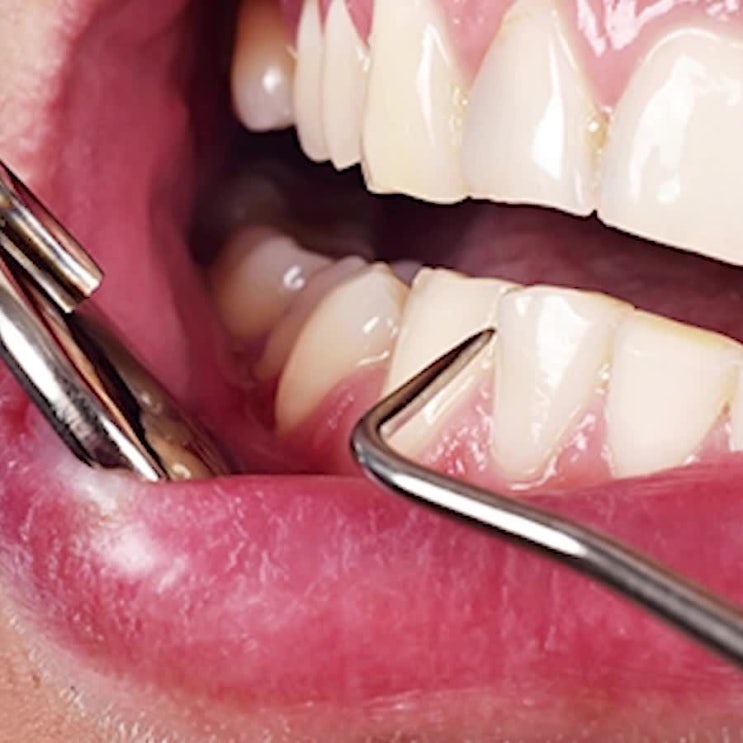

애월읍스케일링 시큰한 통증과 출혈로 인한 오해

스케일링 직후부터 느껴지는 불편한 증상은 건강한 구강을 유지하기 위해선 단순히 양치질만 잘하는 것이 ...